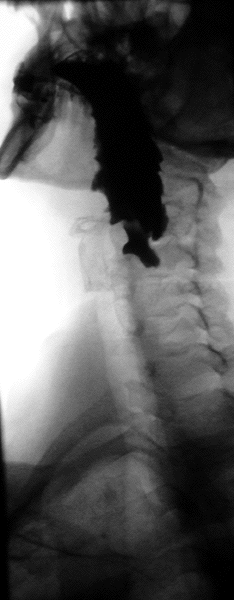

Normal Barium swallow flouroscopic image, showing the ingested barium sulfate being induced down the oesophagus by peristalsis.

Barium swallow

Little or no preparations are required for the study of the larynx, pharynx, and esophagus when studied alone.[10] A thick barium mixture is swallowed in supine position and fluoroscopic images of the swallowing process are made. Then several swallows of a thin barium mixture are taken and the passage is recorded by fluoroscopy and standard radiographs. The procedure is repeated several times with the examination table tilted at various angles. A total of 350-450 mL of barium is swallowed during the process.[11]